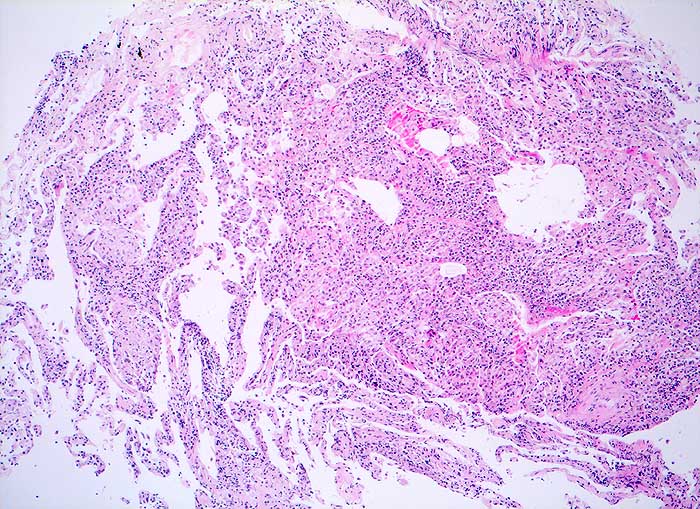

Die exogene allergische Alveolitis (Hypersensitivitätspneumonie) ist eine Entzündungsreaktion der Lunge, die bei prädisponierten Individuen durch pflanzliche oder tierische Inhalationsantigene ausgelöst werden kann. Die BAL Befunde hängen vom Stadium der Erkrankung ab. In der perakuten Phase überwiegen neutrophile Granulozyten. Ausserdem sind in den ersten Tagen der Exposition die Mastzellen auf über 1% erhöht (mehr als 3/10 HPF), um nach 1 bis 3 Monaten wieder auf Normalwerte abzufallen. Bei aktiver EAA besteht oft eine extreme Lymphozytose von 60-70%. Bei chronischer Erkrankung sind Schaumzellen, einige eosinophile Granulozyten und als Ausdruck der Fibrose reichlich neutrophile Granulozyten nachzuweisen.

Eine Lymphozytose von mehr als 100x10^6/L in der BAL zusammmen mit einem erniedrigten HS Quotienten von unter 0.5 sind bei entsprechendem klinischen Verdacht vereinbar mit einer exogenen allergischen Alveolitis.